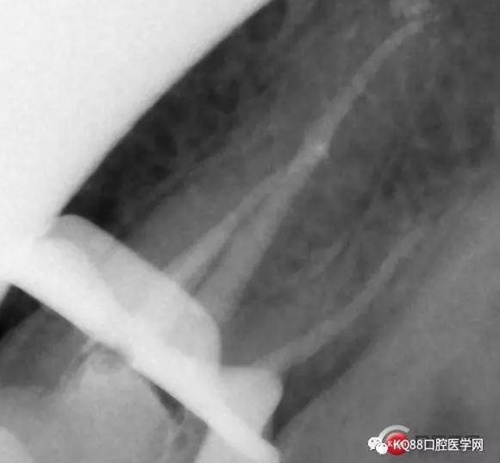

一個上6,常規(guī)的拍片,同上面的方法,根管口定位,乍一看三個根管,但是仔細研究,發(fā)現(xiàn)近中頰根,兩個根管口的C型根管,心理明了以后開始常規(guī)操作。

第一開髓后,只看見三個根管,于是進行三個根管的預備,然后按照髓底解剖圖,進行Mb2探查,近中頰根與腭根連線,遠中頰根向其做垂直線,一般都在這條線附近,于是我開始去髓底白色鈣化,終于找到了Mb2,有鈣化,但是疏通后,到達根方,于是拍攝插針片。

四個根管成型,只是近中兩個根管融合為一個,典型的C型根管。最后開始根充,射片。